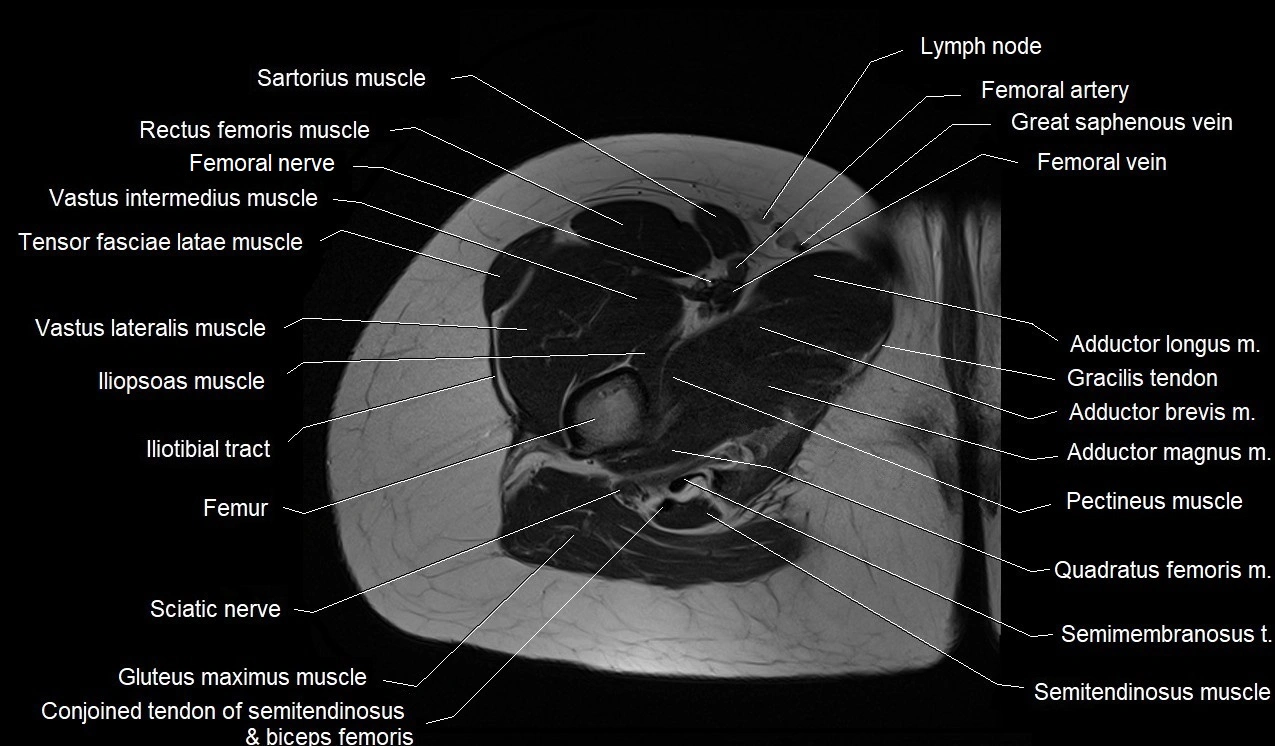

- Conjoint tendon of biceps femoris & semitendinosus

- Femoral artery

- Femoral nerve

- Femoral vein

- Femur

- Gluteus maximus muscle

- Gluteus medius muscle

- Gluteus minimus muscle

- Iliopsoas muscle

- Iliotibial tract

- Obturator externus muscle

- Pectineus muscle

- Quadratus femoris muscle

- Rectus femoris muscle

- Sartorius muscle

- Semitendinosus muscle

- Tensor fasciae latae muscle

- Vastus intermedius muscle

- Vastus lateralis muscle

- Vastus medialis muscle